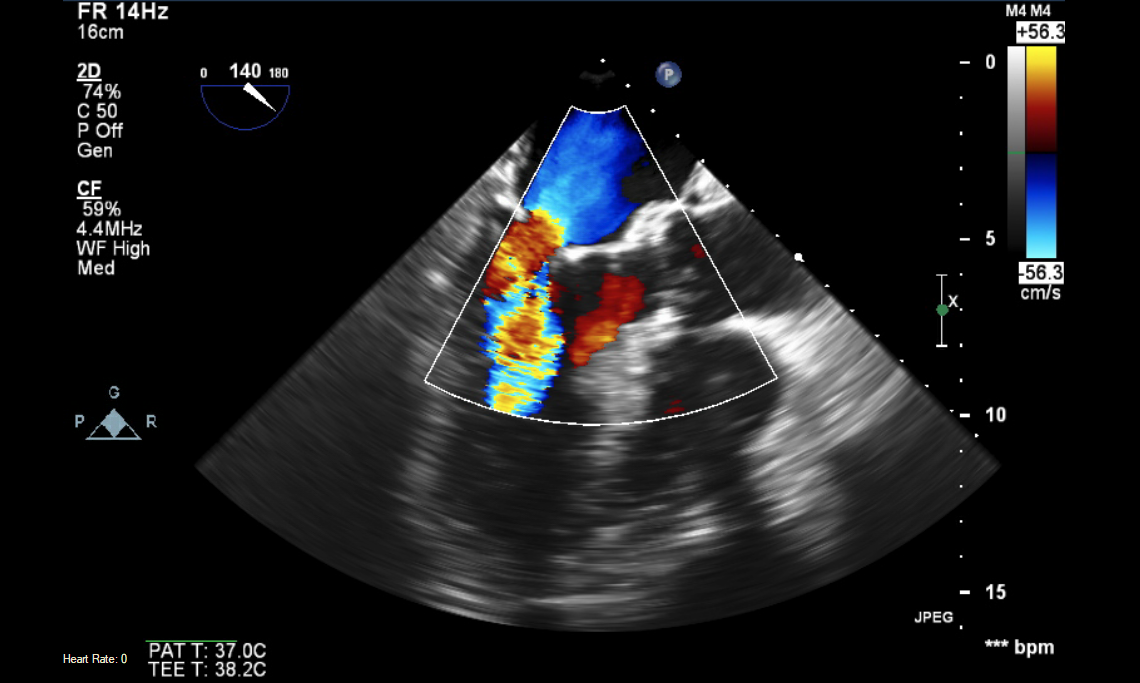

A daily TEE case study, delivered to your email. Quick, focused clinical information. Have extra time? Review the archives anytime to complete them all.

More in-depth case studies, delivered weekly. More echo views, more patient history, more discussion.